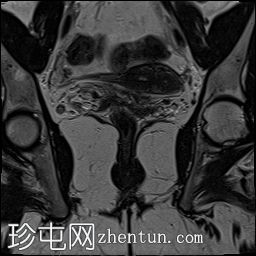

冠状位

斜位T2加权像

子宫外底轮廓清晰,肌层较厚,将子宫内膜腔分隔成两个腔,纤维层较薄,向下延伸至宫颈外口。子宫内膜厚度正常,两个子宫腔交界区清晰,未见明显的实性局灶性病变。

本病例展示了典型的纵隔子宫影像学表现:增厚的肌层隔膜将子宫内膜腔分隔成两个腔,并有一层薄的纤维隔膜延伸至子宫颈外口水平,符合完全纵隔子宫的特征。

纵隔子宫是最常见的先天性子宫畸形,可能导致流产率升高。

磁共振成像(MRI)是目前首选的影像学检查方法。

在MRI图像上,纵隔子宫通常大小正常,但每个子宫腔的形态均小于正常子宫腔。

隔膜可能由纤维组织(T2信号低)、肌层组织(中等信号)或两者共同构成,如本病例所示。